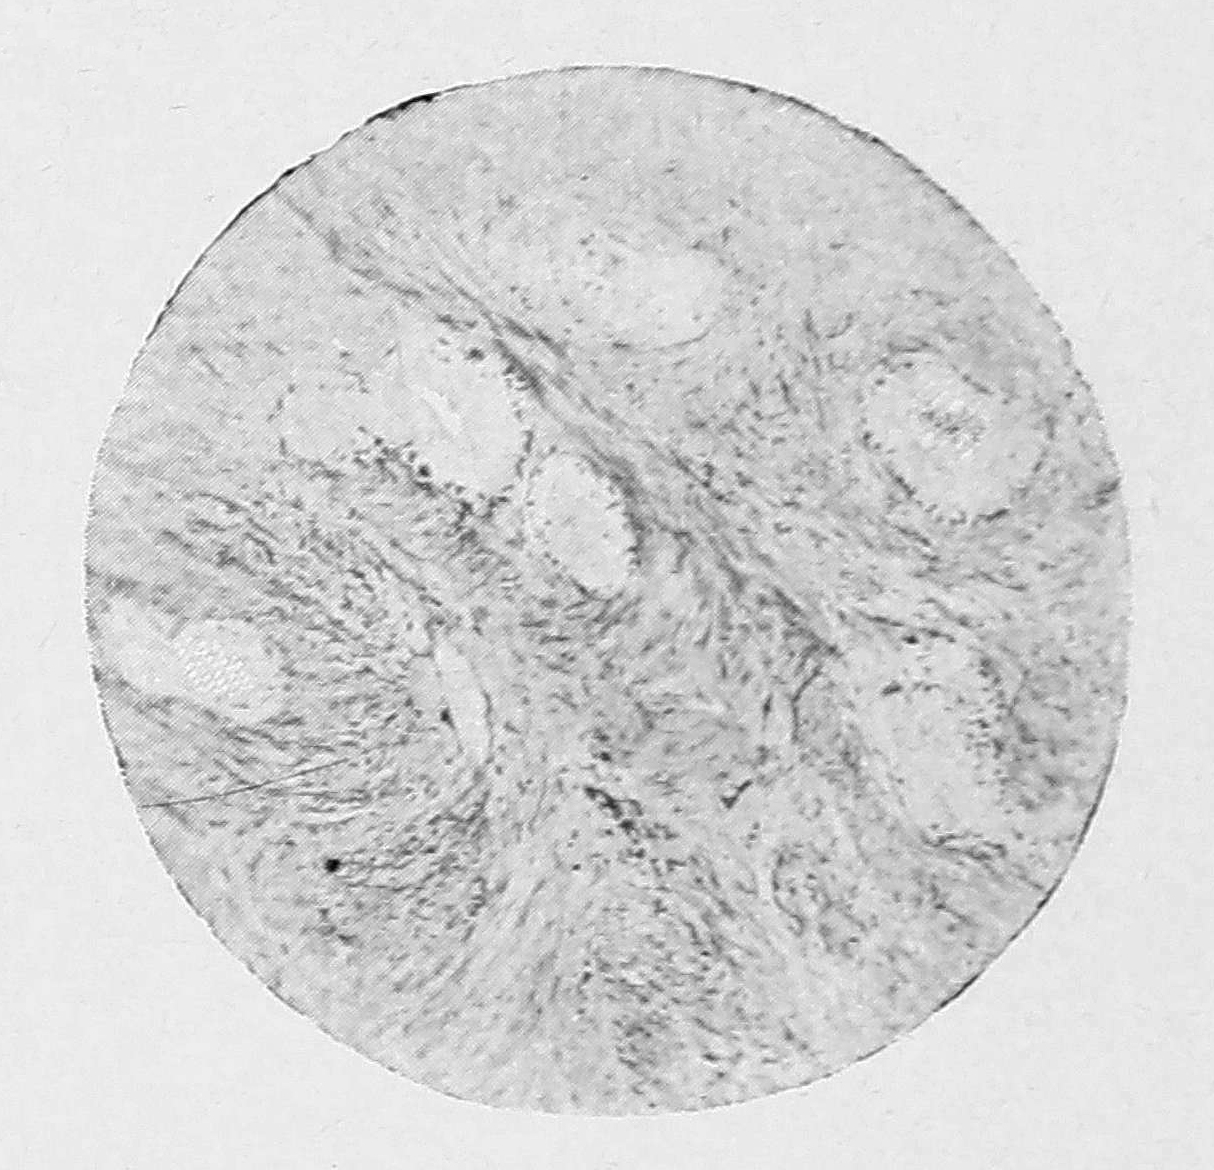

Лучшие, в смысле положительного эффекта прививок, результаты получались у нас в тех случаях, когда частицы соскоба и в особенности мельчайшие кусочки эндометрия были фиксированы на определенных местах образованием искусственных складок брюшины. В опытах этой группы удавалось получить на месте прививки образование конгломерата кистовидных полостей, из которых некоторые достигали величины небольшой горошины. Стенки отдельных полостей и перегородки между ними состояли из волокнистой соединительной ткани, в которой кое-где можно было видеть незначительную примесь гладких мышечных волокон. Внутренняя поверхность этих кист была покрыта одним слоем эпителия, который обычно имел вид вполне жизнеспособного и состоял из цилиндрических клеток, местами с ясно выраженными мерцательными ресничками. В более об’емистых полостях эпителий под влиянием чисто-механических моментов растяжения становился ниже и ресничек уже не обнаруживал. Под слоем эпителия кистовидных полостей, — в особенности более мелкого калибра, — можно было обнаружить в большем или меньшем количестве богатую клетками ткань стромы эндометрия, которая в полостях более значительного об’ема оказывалась сильно редуцированной. Остается еще добавить, что наклонности со стороны кистовидных полостей к проростанию вглубь подлежащих тканей установить мы не могли и, в частности, вростания в ткань яичника ни разу не наблюдали (см. рис. 4).

Рис. 4. Часть железистых кистовидных разростаний на месте прививки эндометрия в брюшинный карман около яичника кролика. Zeiss, Apochr. 16, Comp.-ocul. 4.

Особенно хорошо выраженные железистые разростания получили мы при пересадке кусочков измельченного эндометрия в толщу мышц передней брюшной стенки, — железистые полости, окруженные более или менее резко выраженным поясом стромы, выстланы были внутри цилиндрическим эпителием, обнаруживавшим все признаки жизнеспособности. Значительного растяжения железистых образований в кистовидные полости здесь не наблюдалось (см. рис. 5).

Рис. 5. Железистые включения на месте прививки эндометрия в толщу мышц передней брюшной стенки у кролика. Zeiss, Apoch. 16. Com.-ocul. 6.